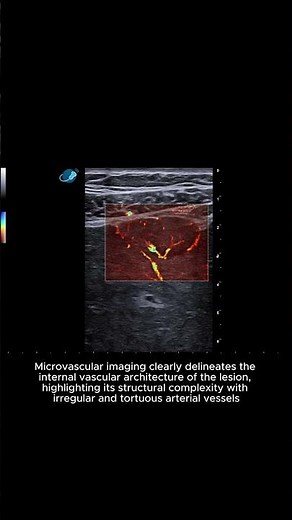

Liver - Hepatocellular carcinoma - Heterogeneous nodular lesions - Clip 1 B-mode + Color + microV

Liver - Hepatocellular carcinoma - Heterogeneous nodular lesions -

…

SonoVerse – Visual Ultrasound Glossary